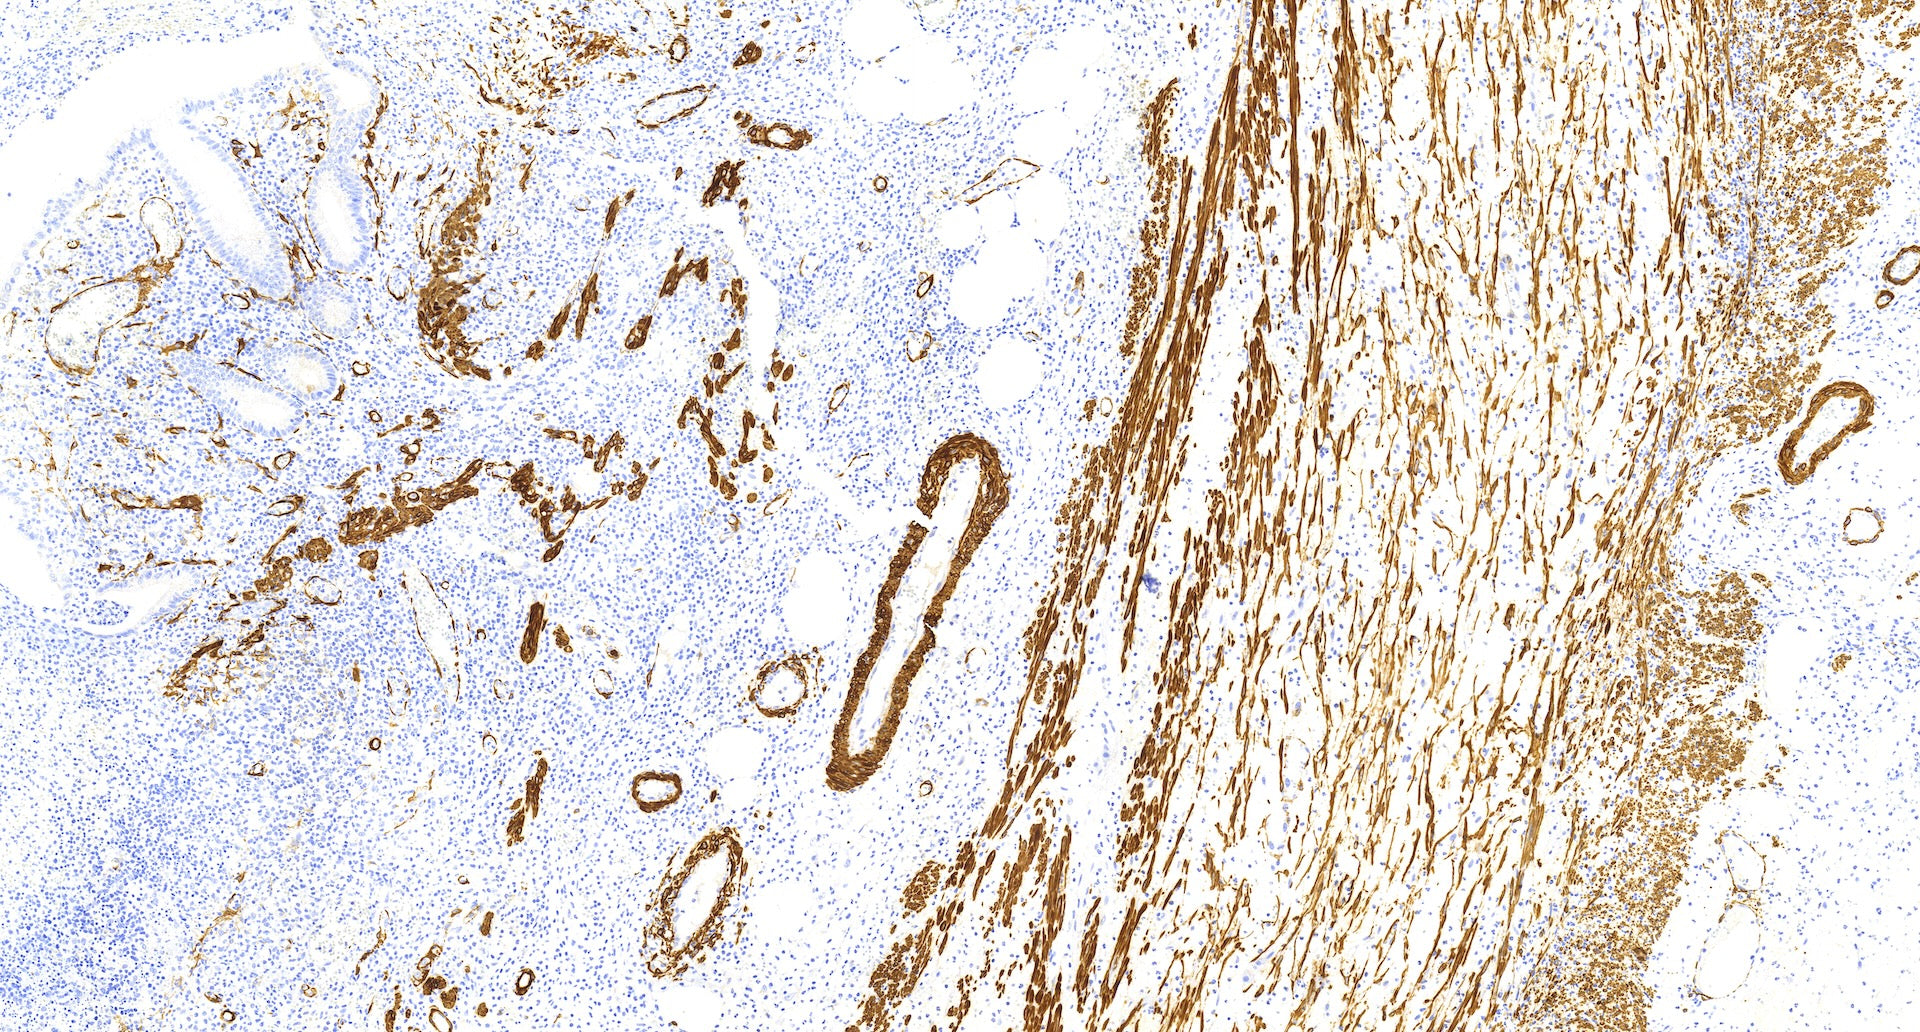

The smooth muscle actin (SMA) marker has been widely used in various contexts. The two commonly used antibodies for SMA detection are anti-SMA and muscle-specific actin (clone HHF-35). SMA is known as a sensitive marker for myoepithelial differentiation. However, it lacks specificity as any cell with significant actin expression will show positive staining for SMA. In breast tissue, myofibroblasts and blood vessels typically stain positive for SMA. This can pose challenges in cases where there are myofibroblasts or blood vessels in close proximity to the epithelial lesion being examined, such as in sclerosing adenosis, radial scars, papillary lesions, or ductal carcinoma in situ (DCIS).

Despite its lack of specificity, SMA remains a useful marker due to its high sensitivity. It helps in resolving differential diagnoses in a significant number of cases. By considering the staining pattern and context, pathologists can interpret the results and differentiate between different lesions.